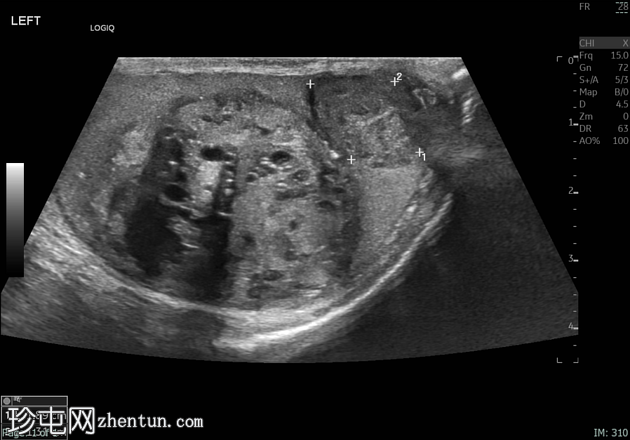

2.png

左侧睾丸肿大,体积约56 mL,可见弥漫性微结石,以及三个内部等回声病灶,伴囊性变、微钙化和明显血流信号,最大病灶大小约4.8 x 3.2 cm。

未见腹主动脉旁或髂淋巴结肿大。